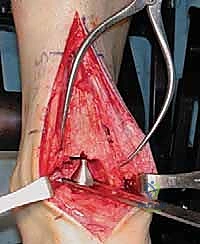

3. تحضير العظام باستخدام أدوات التوجيه

هنا تبرز روعة نظام INBONE™. يتم استخدام أدوات توجيه خاصة (Jigs) لضمان المحاذاة المثالية. يقوم الجراح بإزالة الأجزاء التالفة من غضروف وعظم الظنبوب (Tibia) والقعب (Talus) بدقة متناهية بالملليمتر.

4. إعداد القناة النخاعية وتركيب الساق (Stem)

يتم عمل ثقب دقيق في القناة النخاعية لعظمة الساق. يتم إدخال القطع المعيارية (Modular Stem Pieces) واحدة تلو الأخرى حتى يتم تحقيق التثبيت العميق والمستقر داخل العظم. هذا هو سر قوة نظام INBONE.